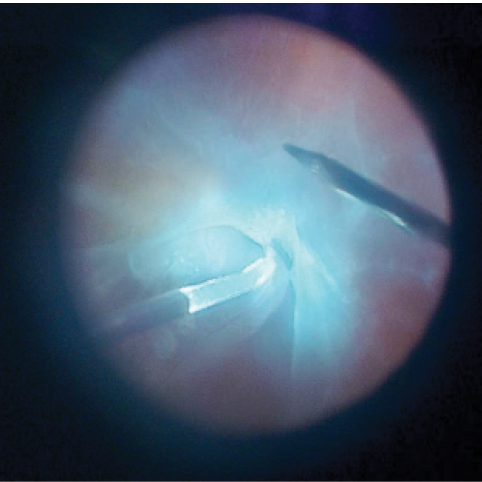

Figure 1. Case No. 1: Heads-up bimanual dissection of PVR using forceps and a lighted pick.

A 79-year-old woman presented with light perception vision, a subluxated posterior chamber intraocular lens (IOL), and a recurrent total retinal detachment (RD) with proliferative vitreoretinopathy (PVR) in the left eye (OS) 2 months after undergoing pars plana vitrectomy (PPV), scleral buckle, and endolaser for repair of her primary rhegmatogenous RD. Her IOL became unstable during the primary RD repair, and postoperatively it was noted to be subluxated. She underwent 25-gauge PPV with membrane peeling, relaxing retinectomy, injection of perfluorooctane (PFO), endolaser, and injection of silicone oil to repair the RD (Figure 1).

During the same surgery, the IOL was fixated to the sclera using a sutureless intrascleral fixation technique.7 Peripheral membrane peeling was achieved using a bimanual technique with a lighted pic and forceps, and these maneuvers were easily completed with the help of heads-up visualization. At the most recent follow-up visit, 3 months after her second surgery, the patient’s retina was attached and she had hand motions vision.